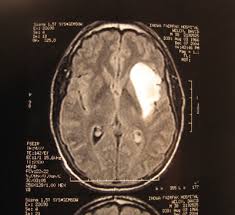

Do cell phones really cause brain cancer?

I was having a discussion about cell phones and brain cancer with my wife yesterday. When will we (as a health care community) decide that we have enough evidence to either substantiate or refute whether cell phones cause brain cancer? According to CNN, a report from the World Health Organization on a decade-long investigation called Interphone will show a "significantly increased risk" of some brain tumors "related to use of mobile phones for a period of 10 years or more." I don't think we've ever really looked at 10+ years of data in the past.